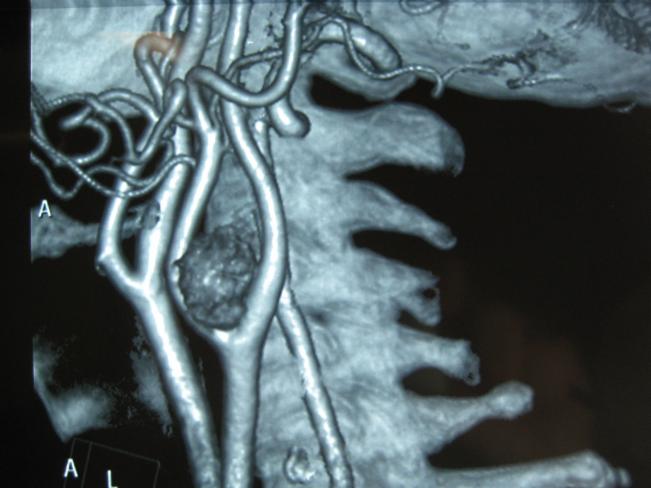

- ISQUEMIA CEREBRO-VASCULAR

- QUEMODECTOMAS.